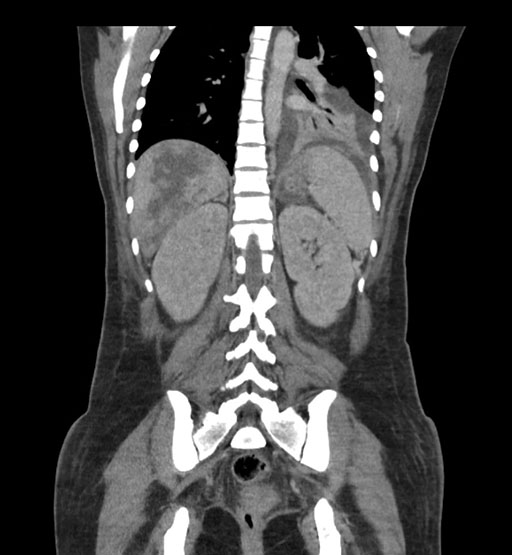

Coronal Venous